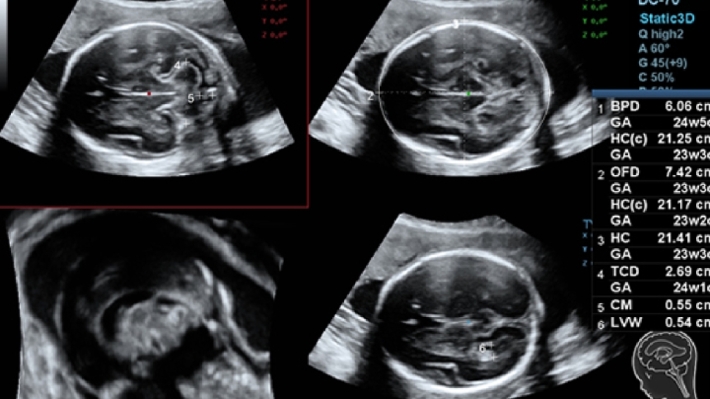

УЗИ-аппарат Mindray DC-70 — это современная ультразвуковая система экспертного класса, предназначенная для проведения диагностических исследований в различных областях медицины, включая кардиологию, акушерство и гинекологию, абдоминальные и сосудистые исследования. Аппарат сочетает высокое качество изображения с широким набором функциональных возможностей, что делает его эффективным инструментом для диагностики.

• Многофункциональность: Поддержка различных режимов сканирования, включая 2D, 3D/4D, цветное допплеровское картирование и другие, позволяет использовать аппарат для широкого спектра медицинских задач;

• Smart OB™ — программа автоматического расчета основных акушерских показателей;

• Smart NT — программа для автоматического определения и расчета толщины воротникового пространства у плода;

Изображения